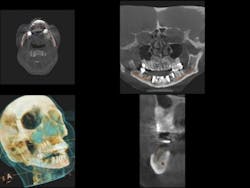

The solution to this problem is to simply measure this space with the esthetic functional lip ruler (gdit.us). Figure 1a shows the esthetic functional ruler (EFLR) for measuring in millimeters both the maxillary and mandibular ridge crest to resting lip. Figure 1b shows the stops that rest on the ridge crest. Figure 2a shows a patient displaying excess show of mandibular teeth and occlusal plane discrepancy. Figure 2b demonstrates EFLR measurement of 17 mm from the resting lower lip to the premandibular crest. Figure 3a denotes five implants and a cast metal bar frame. Figure 3b measures the height of the bar from the ridge crest to the top of the bar. Figure 4a shows 9 mm of tooth exposed above the lower lip. Figure 4b demonstrates the height of the mandibular prosthesis attached to the bar measuring 26 mm.